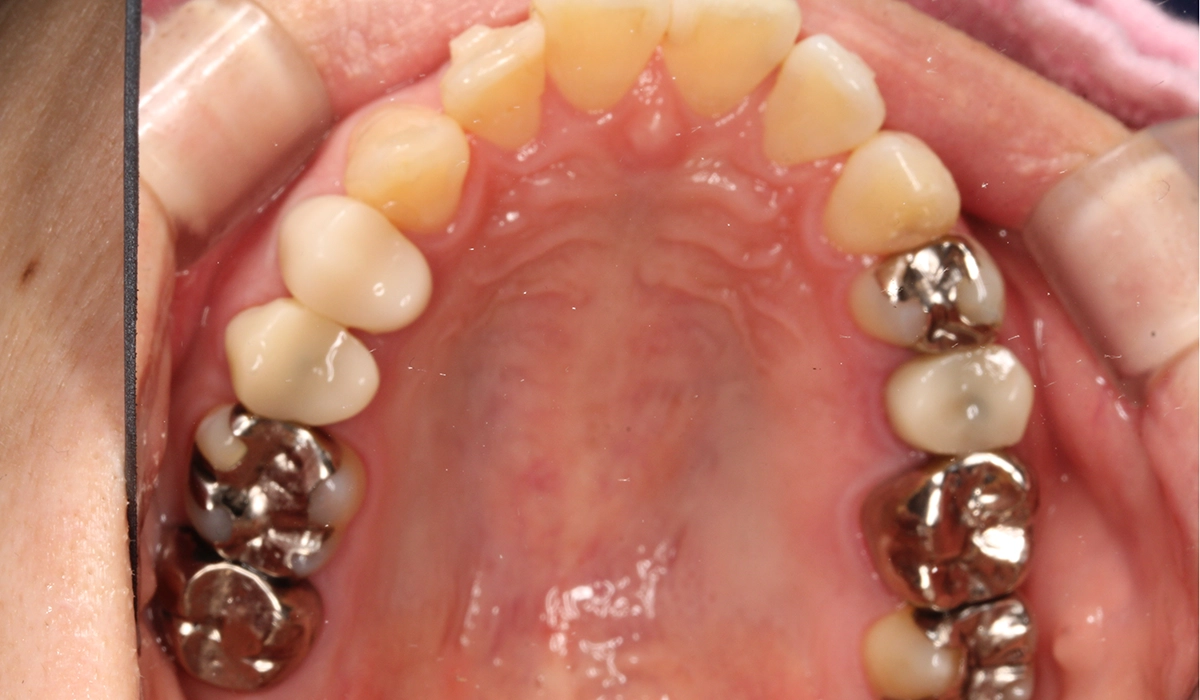

術前:上顎

術後:上顎